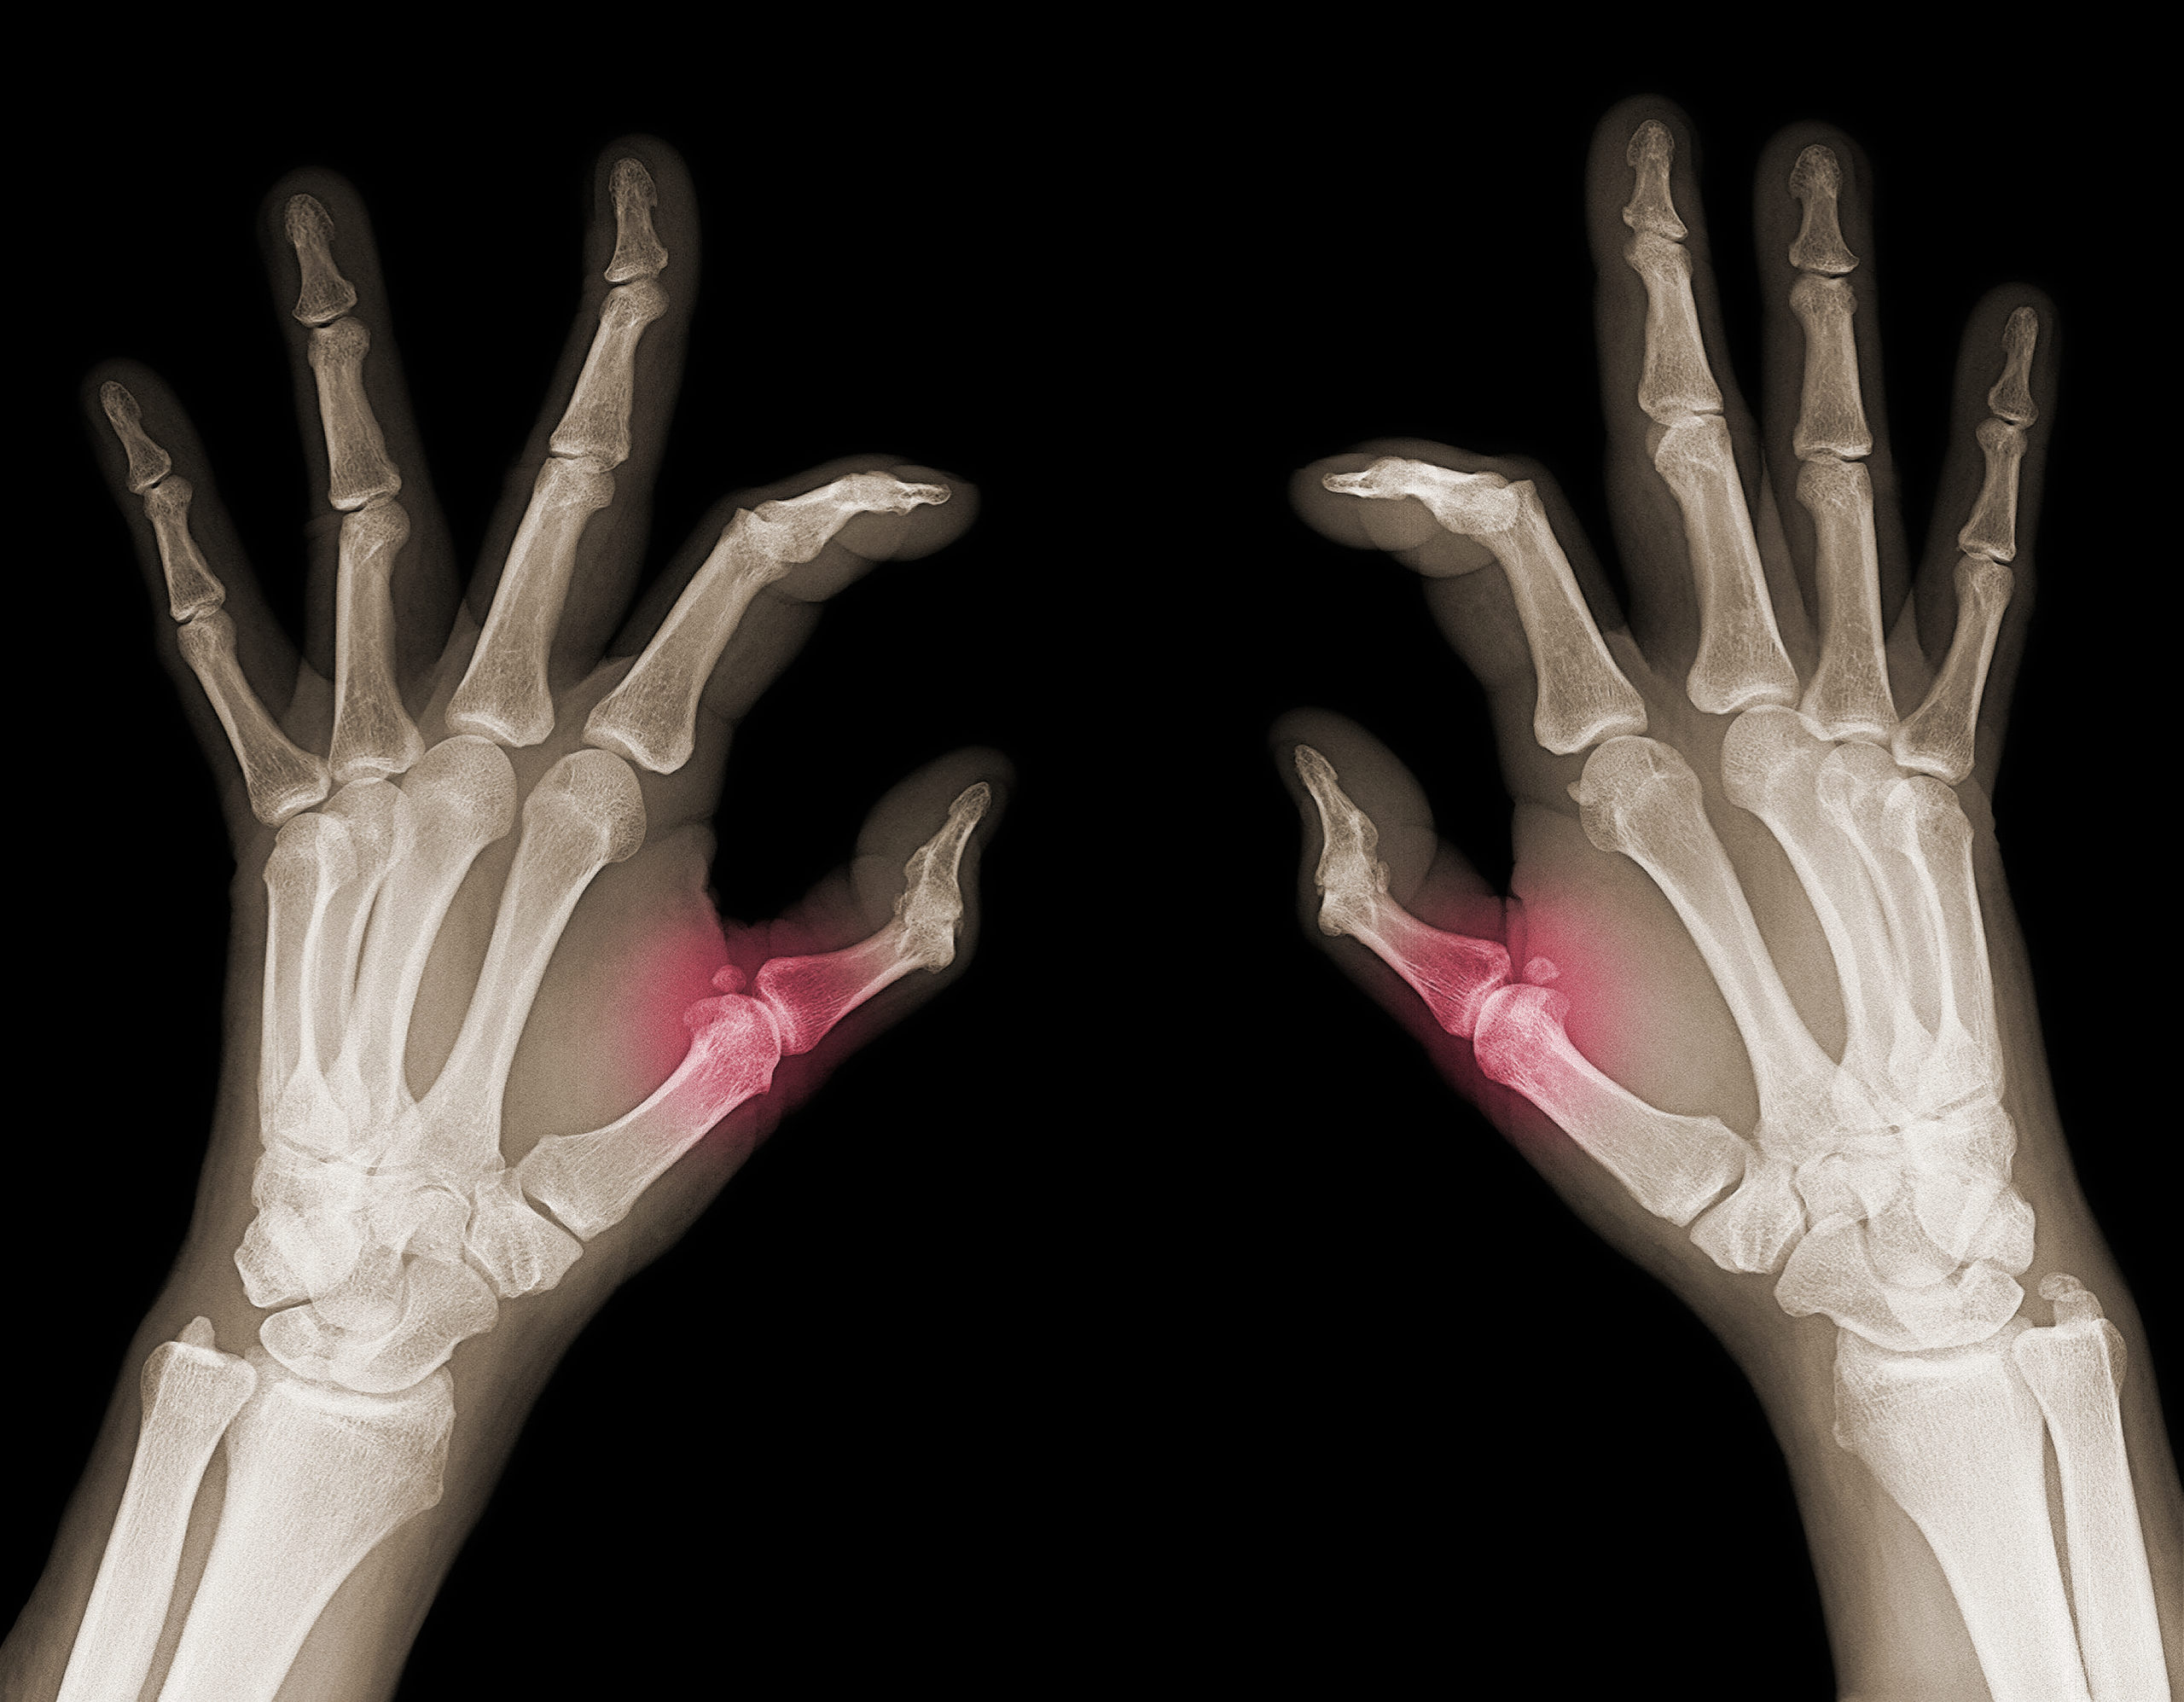

In their project, FAU researchers consider different types of radiation that we come into contact with, for example, during medical treatments or in nature and that can pose a risk to us. This includes X-rays, an ionizing radiation that can be used, for example, to treat tumors. In addition, there is the alpha radiation emitted by radon, which is produced via naturally occurring uranium. All of these types of radiation are known to have anti-inflammatory effects and can positively influence bone stability in low doses, but in high doses they are more likely to promote inflammation and pose a cancer risk.